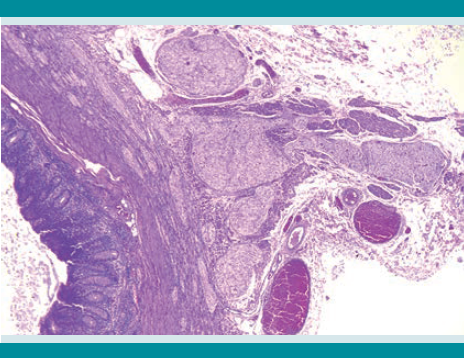

En el aspecto macroscópico inicialmente se estudiaron dos segmentos de íleon terminal de 6 y 4 cm de longitud mayor y menor, respectivamente. Los especímenes mostraron a la serosa sumamente engrosada y la pared indurada e irregular. El calibre de la luz estaba muy disminuido. El colon se recibió en dos segmentos que midieron, en conjunto, 34 cm de longitud. El aspecto era semejante al del intestino delgado.

Al microscopio, la lesión consiste en una proliferación muy prominente de troncos y plexos nerviosos que afecta todas las áreas del intestino explorado y diferentes partes de la pared. En las muestras de íleon terminal, apéndice cecal, colostomía y sigmoides se apreciaban cambios en la submucosa y en la pared muscular. En las muestras de ciego y colon transverso los cambios se localizaban, predominantemente, en los plexos mientéricos. Todos los cambios observados sirvieron de base para establecer el diagnóstico de ganglioneuromatosis difusa.